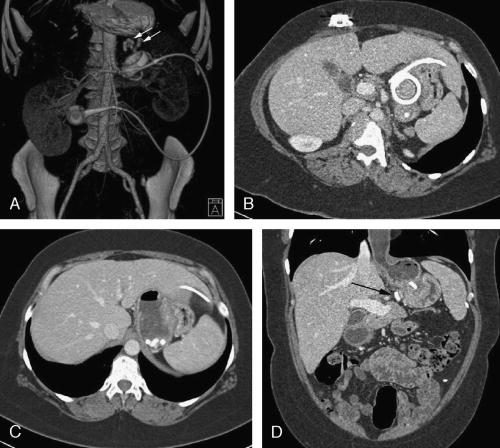

Laparoscopic adjustable gastric banding (LAGB) is a widely performed surgical procedure for morbid obesity in Europe and Australia. An upper gastrointestinal examination is usually used to assess for band placement and possible complications. Computed tomography (CT) is not used routinely but may be beneficial to evaluate LAGB and possible complications. Also, LAGB may be incidentally demonstrated on CT. We report 2 patients with LAGB that was well demonstrated on multidetector CT with multiplanar reformation and 3-dimensional imaging.

Laparoscopic adjustable gastric banding (LAGB) was introduced in the early 1990s and is today the most commonly performed surgical procedure for morbid obesity in Europe and Australia. It has been shown to result in significant long-term weight loss. However, the Food and Drug Administration did not approve its use in the United States until 2001, and LAGB represents less than 10% of bariatric procedures in the United States. Laparoscopic adjustable gastric banding contains 3 main parts: an adjustable gastric band, connection tubing, and an access port/reservoir. An upper gastrointestinal (GI) examination is usually used to assess for placement of band, pouch size, stoma size, and possible complications such as extraluminal leak or obstruction. Computed tomography (CT) is not used routinely after LAGB but may be beneficial to evaluate gastric banding and possible complications. Also, gastric banding may be incidentally demonstrated on CT performed for other indications. We report 2 cases of LAGB that was well demonstrated on multidetector CT with multiplanar reformation and 3-dimensional imaging.

Upper GI examination after LAGB procedure is important to assess placement of the band, size of the pouch and stoma, and possible complications such as extraluminal leak or obstruction. Computed tomography is not used routinely after LAGB and may not be technically feasible in the most severely obese patients. However, CT may be beneficial to evaluate for a source of infection and to assess for complications. In patients with normal LAGB, CT images should reveal the radiopaque band around the proximal stomach and the attached connecting tubing extending through the anterior abdominal wall to the subcutaneous port. Computed tomography with multiplanar reformation and 3-dimensional imaging is helpful to delineate the entire LAGB, the location and orientation of the band relative to the stomach, the size of the gastric pouch, and possible complications such as band erosion, gastric herniation, and infection.